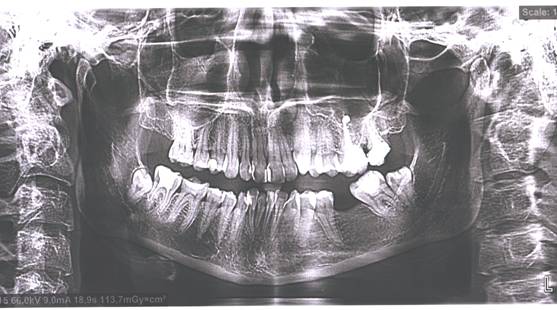

Пациентки Р. рекомендовали выполнить «2D исследование» - панорамную рентгенографию. Рис. 1

Рис. 1 Панорамная рентгенография пациентки Р., исходное состояние.

При анализе панорамной рентгенографии обнаружено

следующее: включенный дефект нижней челюсти в области 35-37 зубов; дистопия и ретенция 48-38 зубов; скученность зубов фронтального

участка нижней челюсти; нарушение соотношений 13 и 43, 23 и 33 зубов; эндодонтическое лечение 47, 26, 27

зубов; нарушение окклюзионных взаимоотношений зубов верхней и нижней челюстей;

неравномерность окклюзионной кривой, деформация

структуры головки ВНЧС справа, ее дистализация за

счет деформации пломбы в 46 зубе и снижения высоты прикуса; разница

анатомического объёма головок ВНЧС слева и справа; несимметричное расположение

головок суставов левой и правой сторон; суставная щель слева практически не

прослеживается.

На основании жалоб и анализа

панорамной рентгенографии пациентке Р. был установлен диагноз - хронический

травматический (окклюзионный) артрит ВНЧС справа с

дистальным смещением суставной головки нижней челюсти.